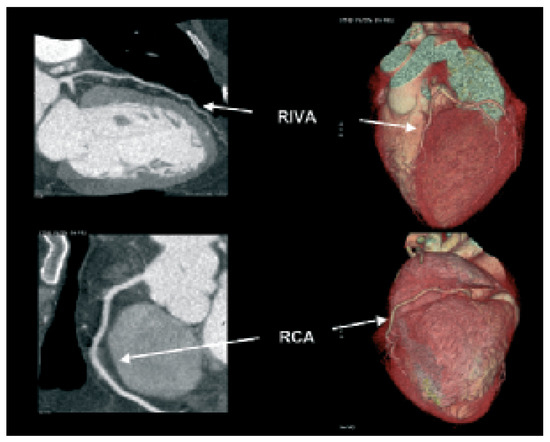

Biventricular pacing is an accepted therapy in patients suffering from terminal heart failure. Main obstacle however is the positioning of the left ventricular electrode via coronary sinus as well as its reliable fixation. This article describes in a...